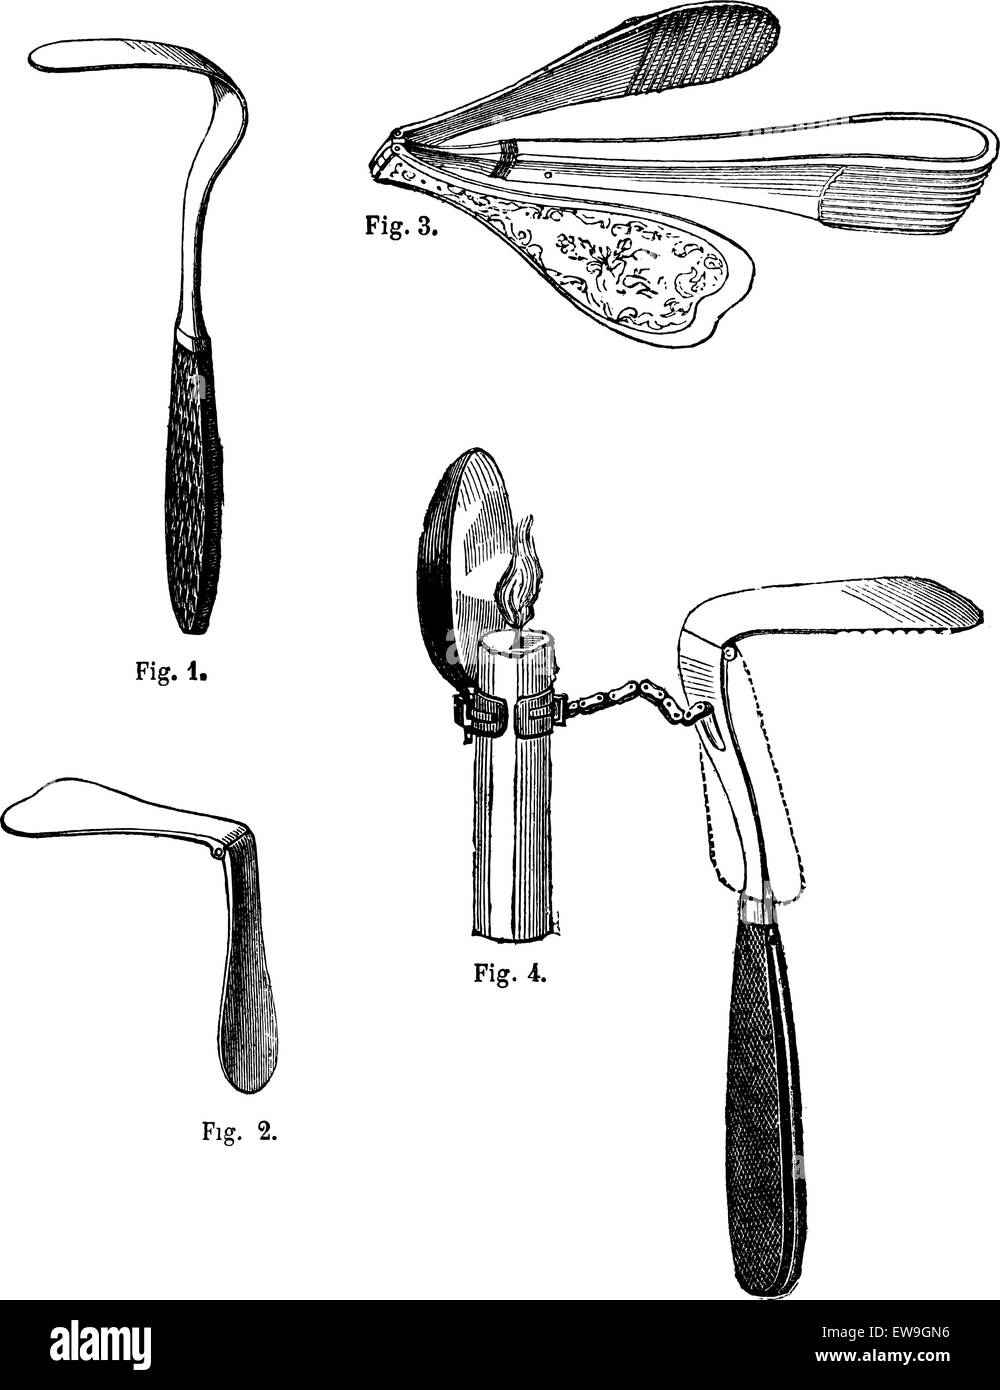

RFEW90NP–Fig 1. Abaisse-langue fixe, Fig.2 abaisse-langue articule, Fig 3. Abaisse-langue articulée, Ricord, Fig 4. Langue maternelle dep

RFEW9GN6–Fig 1. Abaisse-langue fixe, Fig.2 abaisse-langue articule, Fig 3. Abaisse-langue articulée, Ricord, Fig 4. Langue maternelle dep